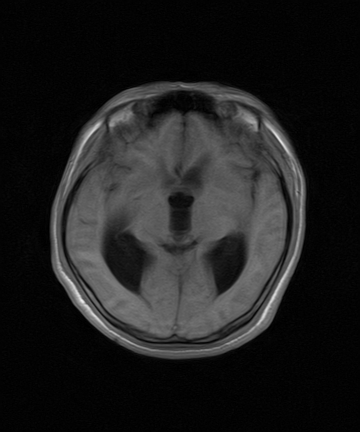

标题: MRI2064:少见病例。男性52,视力下降多年。 [打印本页]

标题: MRI2064:少见病例。男性52,视力下降多年。

四脑室区见混杂信号占位影,脑室系统扩张明显,临近结构显著受压称位,患者52岁,多考虑室管膜瘤可能性大

考虑第四脑室室管膜瘤并梗阻性脑积水;部分性空蝶鞍;左侧上颌窦粘膜下囊肿。

小脑血管母细胞瘤.并外压性脑积水.

比较典型的脉络丛乳头状瘤并脑积水,鉴别小脑蚓部血管母细胞瘤。